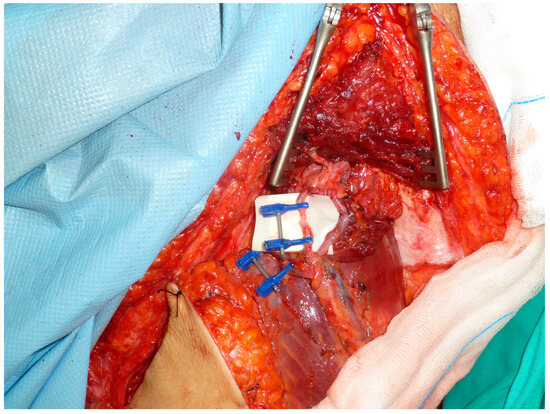

Total Quadriceps Resection in High-Grade Soft-Tissue Sarcomas of the Thigh: Surgical Technique and Long-Term Functional Outcomes in Surviving Patients

by Luis Rafael Ramos Pascua, Paula Casas Ramos, Rubén Álvarez García, Sergio Sánchez Herráez, Cristina Ojeda Thies, Maximiliano Eugenio Negri, Daniel Bustamante Recuenco and Jesús Enrique Vilá Rico

Cancers 2026, 18(1), 37; https://doi.org/10.3390/cancers18010037 - 22 Dec 2025

Background: Reconstruction of the thigh extensor mechanism following wide excision of a soft-tissue sarcoma is difficult. The aim of this study was to describe the outcomes following complete quadriceps resection for large high-grade soft-tissue sarcomas. Methods: Ten patients with AJCC grade IIIB soft-tissue [...] Read more.

Background: Reconstruction of the thigh extensor mechanism following wide excision of a soft-tissue sarcoma is difficult. The aim of this study was to describe the outcomes following complete quadriceps resection for large high-grade soft-tissue sarcomas. Methods: Ten patients with AJCC grade IIIB soft-tissue sarcomas of the anterior thigh were treated with total wide margin quadricectomy, with a mean follow-up of 4 years (range: 51–163 months) in the five surviving patients with conservative surgical procedures. The minimum follow-up period for four of these patients was 8 years. The extensor mechanism was reconstructed with local muscle transfers (eight cases) or a neurotized free flap of the contralateral vastus lateralis (two cases). Results: Four patients died, two due to non-tumor related causes and two due to metastatic disease at 50 months and 43 months. The remaining six were alive and disease-free at the final follow-up. All patients received surgical revision due to wound necrosis. Another patient required an external hemipelvectomy due to early local recurrence of the disease. Functional results of the five patients who remained alive and retained their limb were good or excellent in two cases, acceptable in one, and poor in two, according to their MSTS scores. Average knee flexion was 80° (range: 10–150°). Passive extension was complete in all cases, though no patients achieved it actively. Extensor strength was 2/5 in four patients and 4/5 in the other. Conclusion: Total quadricectomy for high-grade soft-tissue sarcomas of the anterior thigh compartment ensures wide resection margins and local disease control, although local wound complications are common, particularly in older patients. Resection appears to be technically easier if performed distally to proximally in the thigh. Local muscle transfers are more suited for low-demand patients, while neurotized free muscle flaps are mainly an option for young, motivated patients. Full article

Show Figures

Figure 1